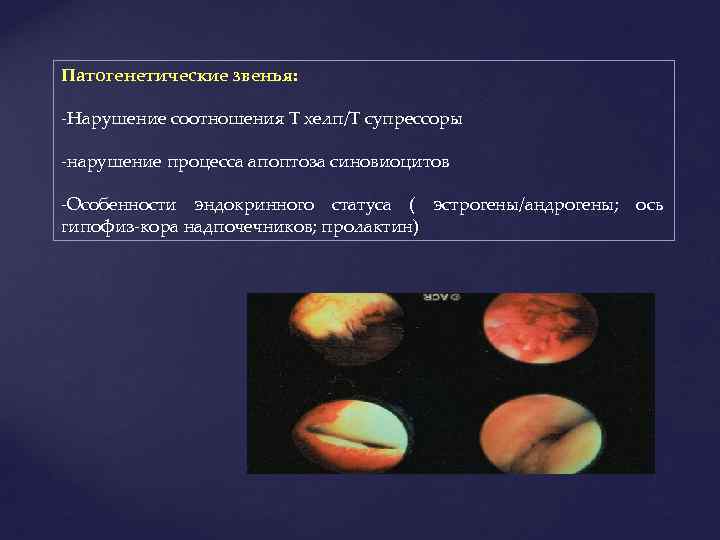

Патогенетические звенья: -Нарушение соотношения Т хелп/Т супрессоры -нарушение процесса апоптоза синовиоцитов -Особенности эндокринного статуса ( эстрогены/андрогены; ось гипофиз-кора надпочечников; пролактин)

Патогенетические звенья: -Нарушение соотношения Т хелп/Т супрессоры -нарушение процесса апоптоза синовиоцитов -Особенности эндокринного статуса ( эстрогены/андрогены; ось гипофиз-кора надпочечников; пролактин)